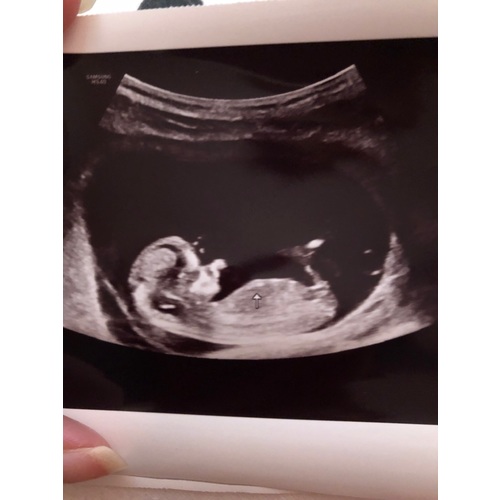

Wat denken jullie dames een meisje of een jongen 💖💙

12 weken en 1 dag. Iemand een idee jongen of meisje 🥰